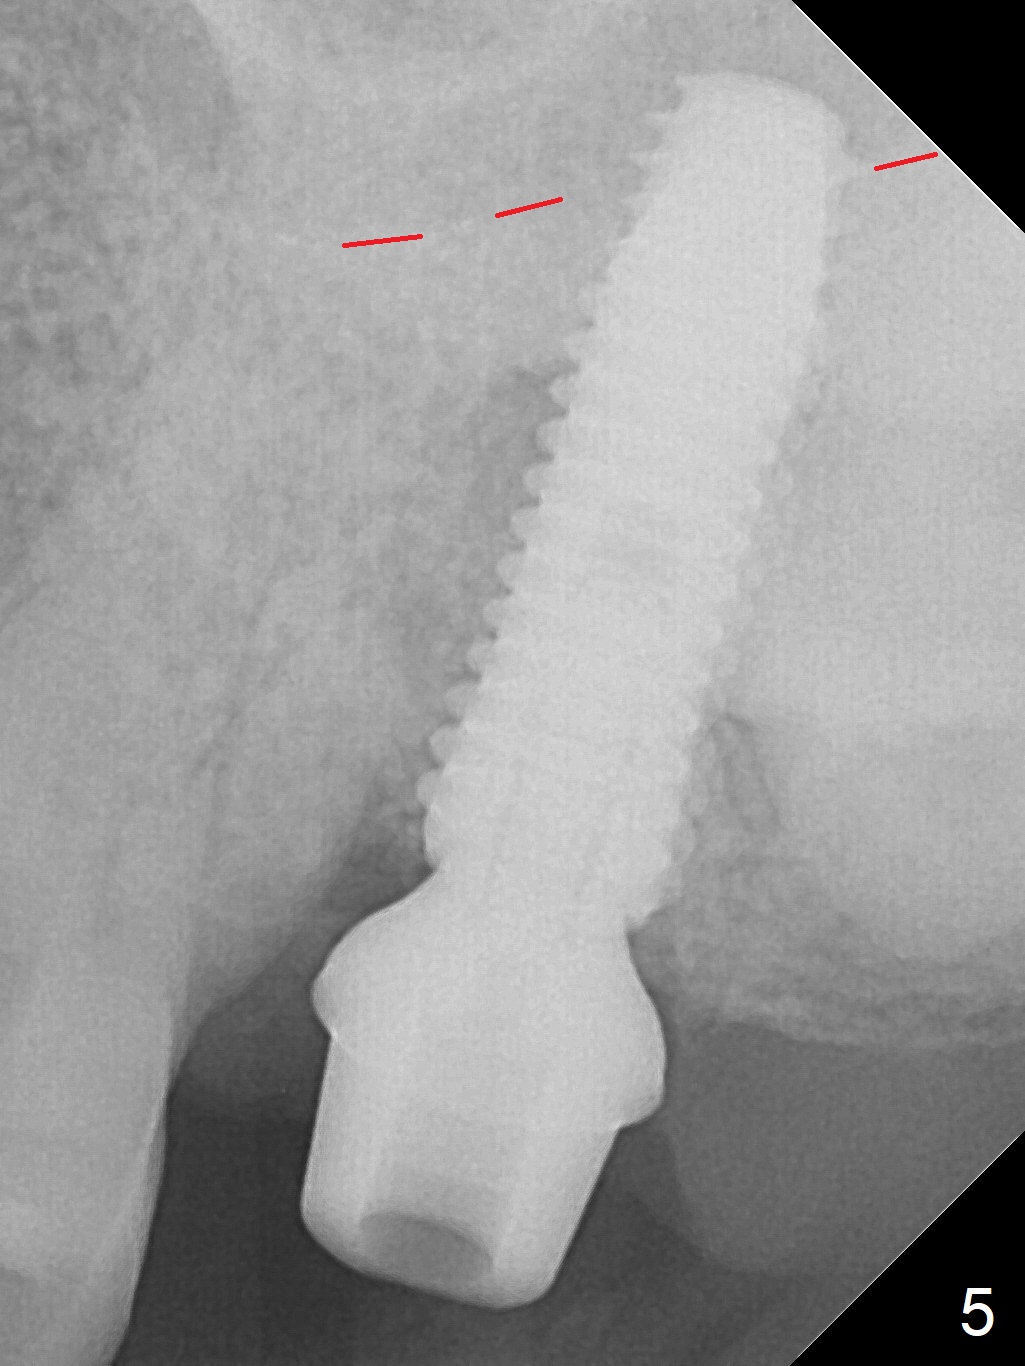

Extraction of the tooth #15 with short clinical crown (suggesting bruxism, Fig.1) reveals a vertical root fracture (Fig.2 <). It seems unnecessary and difficult to create osteotomy in the mesial slope. What can be done is to place starter and 2 mm drills as mesial as possible (Fig.3 (red dashed line: sinus floor). After use of Lindamann bur to move the osteotomy mesially and sequential osteotomy until 3.8x18 mm, a 4.5 mm tap is inserted with clearance from the impacted tooth #16 (Fig.4). A 5x15 mm implant is placed with >60 Ncm with clearance from the 3rd molar (Fig.5,6). If the impacted tooth were removed, the primary stability is expected to be reduced. Impression is taken 6 months postop with 19/20 implants (Fig.7). The bone graft remains in the crestal area immediately and 11 months post cementation (Fig.8,9 *). In the other word, new crestal bone forms after extraction.